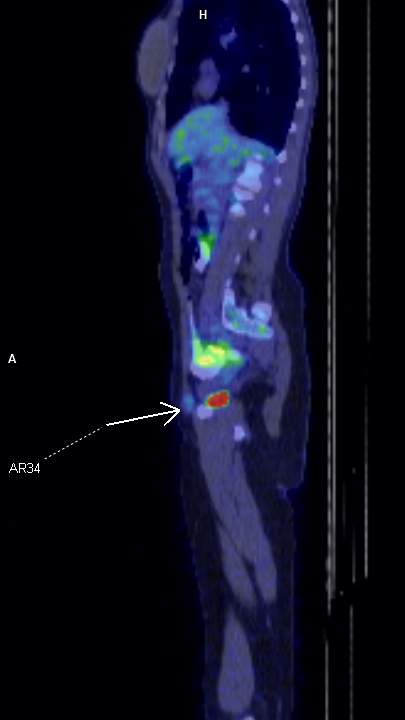

Figura 2: sagital PET-CT la diagnostic iniţial

Endometrioza este o patologie benignă dar cu rată de recurentă mare; cazul prezentat este al unei paciente cu o leziune expansivă de perete abdominal inferior în vecinătatea regiunii inghinale drepte pentru care a efectuat examinare PET CT pentru diagnostic și stadializare datorită suspiciunii de adenopatie de la un melanom malign – iar leziunea nu a avut captare foarte mare. După excizie și examen histopatologic diagnosticul a fost de focar de endometrioza iar examinarea postoperatorie prin rezonanță magnetică nu a evidențiat un rest sau o recidivă locală. Câțiva ani mai târziu se remarcă creșterea volumului local și examinarea prin rezonanță magnetică evidențiază un aspect tipic de endometrioză.